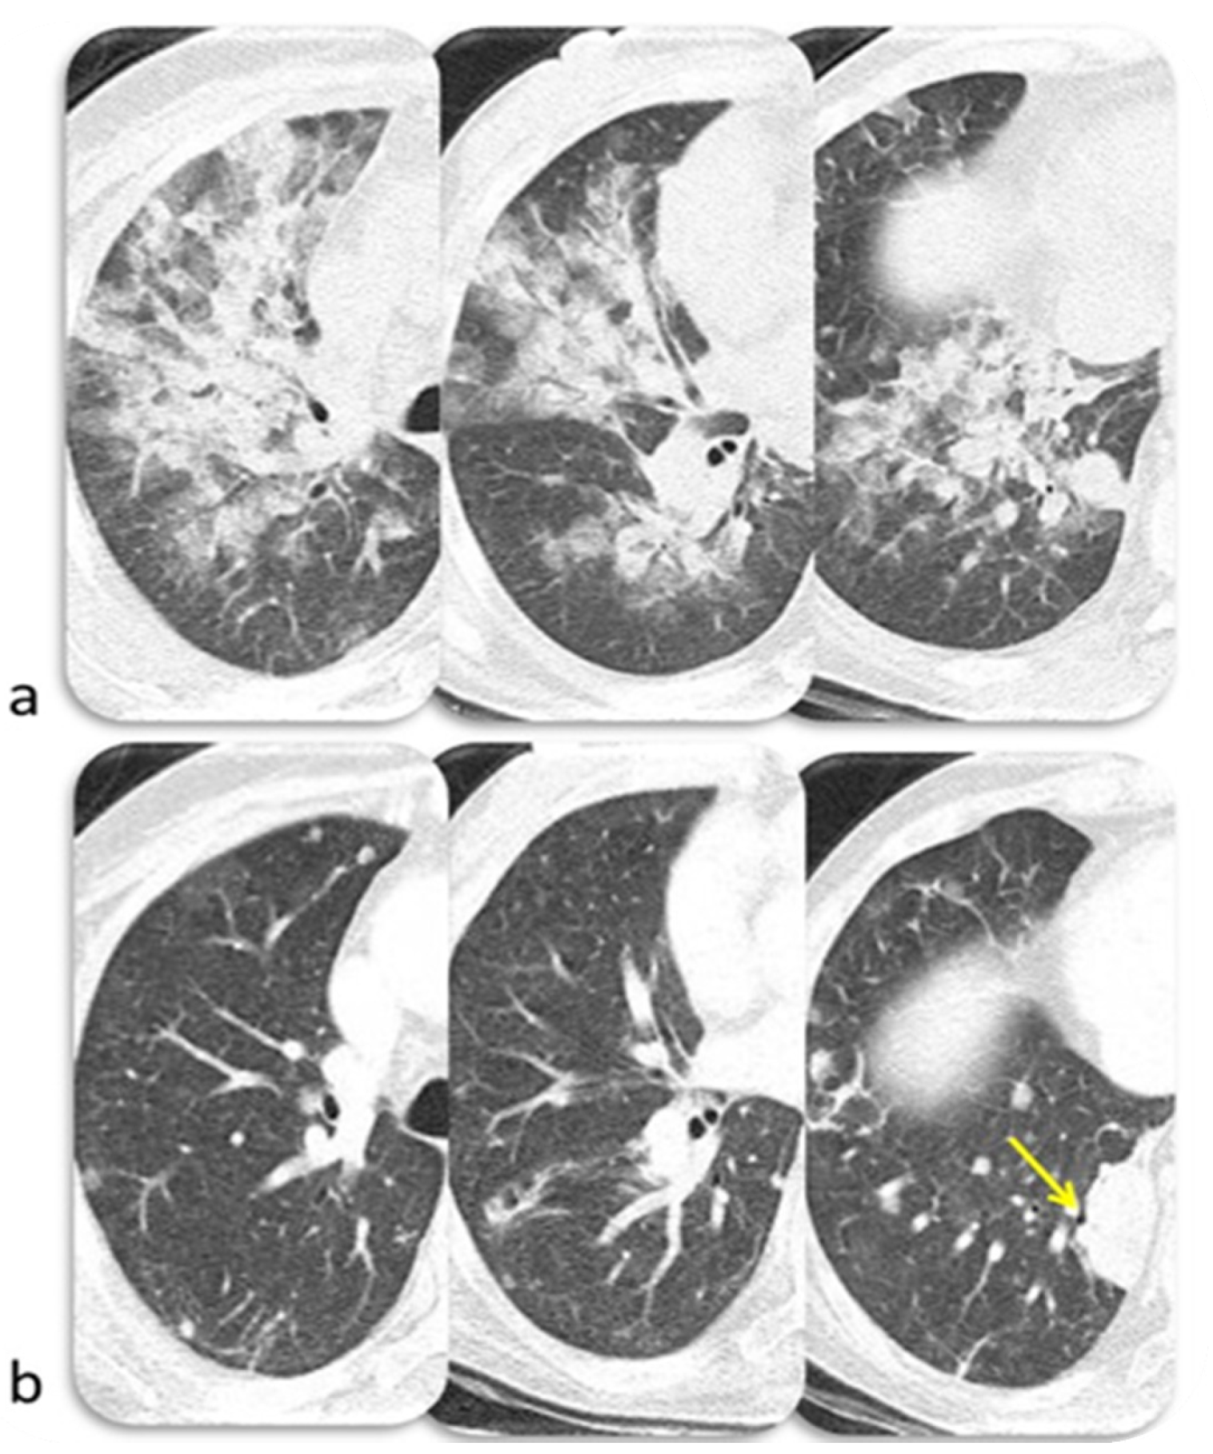

6.3. Lung